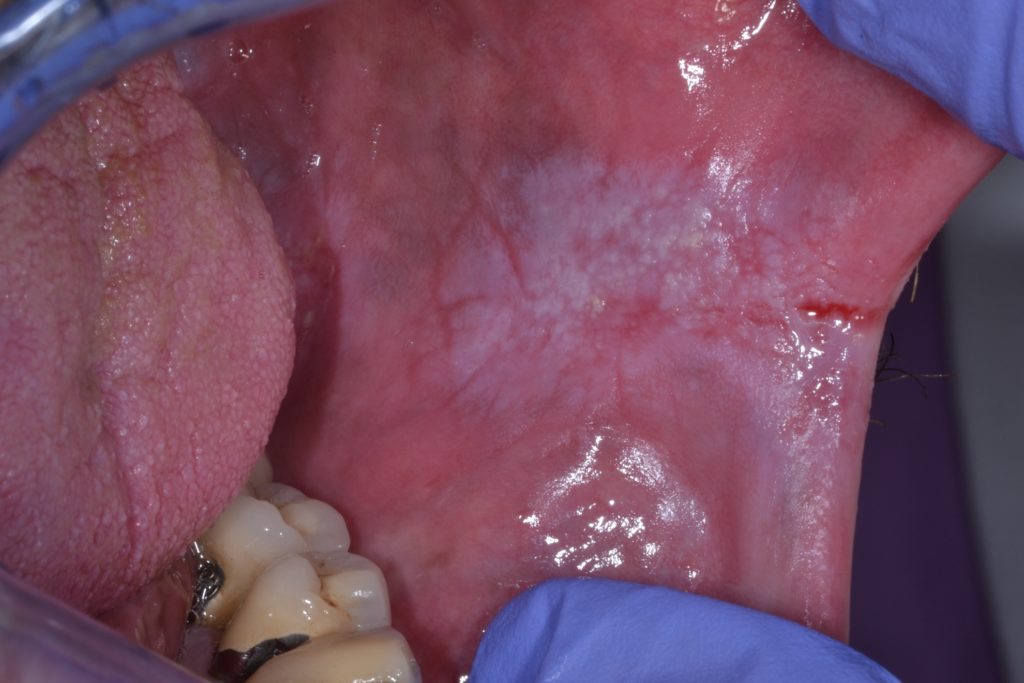

White Spots On Gums Leukoplakia . Leukoplakia is a condition involving thickened white patches on the mucous membranes (lining) of the mouth, gums, and/or. Leukoplakia patches on your tongue, gums, roof of your mouth, or the inside of your cheeks may be: If you accidentally bite the inside of your cheek or burn the roof of your. The patches don’t hurt but they don’t. They may thicken or harden overtime, and they. They are typically harmless, although some doctors think they are precancerous. Leukoplakia describes white patches on the roof of the mouth, tongue, and gums. This mouth condition appears as thick, white patches on the gums, the cheeks and the bottom of the mouth that cannot be scraped. Leukoplakia are small white patches that appear on the gums, the insides of the cheeks, the bottom of the mouth, and the tongue. Leukoplakia is a condition that creates white patches on your tongue, gums or the inside of your cheeks. But not every white patch in the mouth is leukoplakia.

If you accidentally bite the inside of your cheek or burn the roof of your. Leukoplakia describes white patches on the roof of the mouth, tongue, and gums. They may thicken or harden overtime, and they. They are typically harmless, although some doctors think they are precancerous. But not every white patch in the mouth is leukoplakia. Leukoplakia are small white patches that appear on the gums, the insides of the cheeks, the bottom of the mouth, and the tongue. The patches don’t hurt but they don’t. Leukoplakia is a condition involving thickened white patches on the mucous membranes (lining) of the mouth, gums, and/or. This mouth condition appears as thick, white patches on the gums, the cheeks and the bottom of the mouth that cannot be scraped. Leukoplakia is a condition that creates white patches on your tongue, gums or the inside of your cheeks.

White Spots On Gums Leukoplakia Leukoplakia patches on your tongue, gums, roof of your mouth, or the inside of your cheeks may be: Leukoplakia patches on your tongue, gums, roof of your mouth, or the inside of your cheeks may be: This mouth condition appears as thick, white patches on the gums, the cheeks and the bottom of the mouth that cannot be scraped. If you accidentally bite the inside of your cheek or burn the roof of your. Leukoplakia describes white patches on the roof of the mouth, tongue, and gums. Leukoplakia are small white patches that appear on the gums, the insides of the cheeks, the bottom of the mouth, and the tongue. The patches don’t hurt but they don’t. But not every white patch in the mouth is leukoplakia. They may thicken or harden overtime, and they. They are typically harmless, although some doctors think they are precancerous. Leukoplakia is a condition involving thickened white patches on the mucous membranes (lining) of the mouth, gums, and/or. Leukoplakia is a condition that creates white patches on your tongue, gums or the inside of your cheeks.